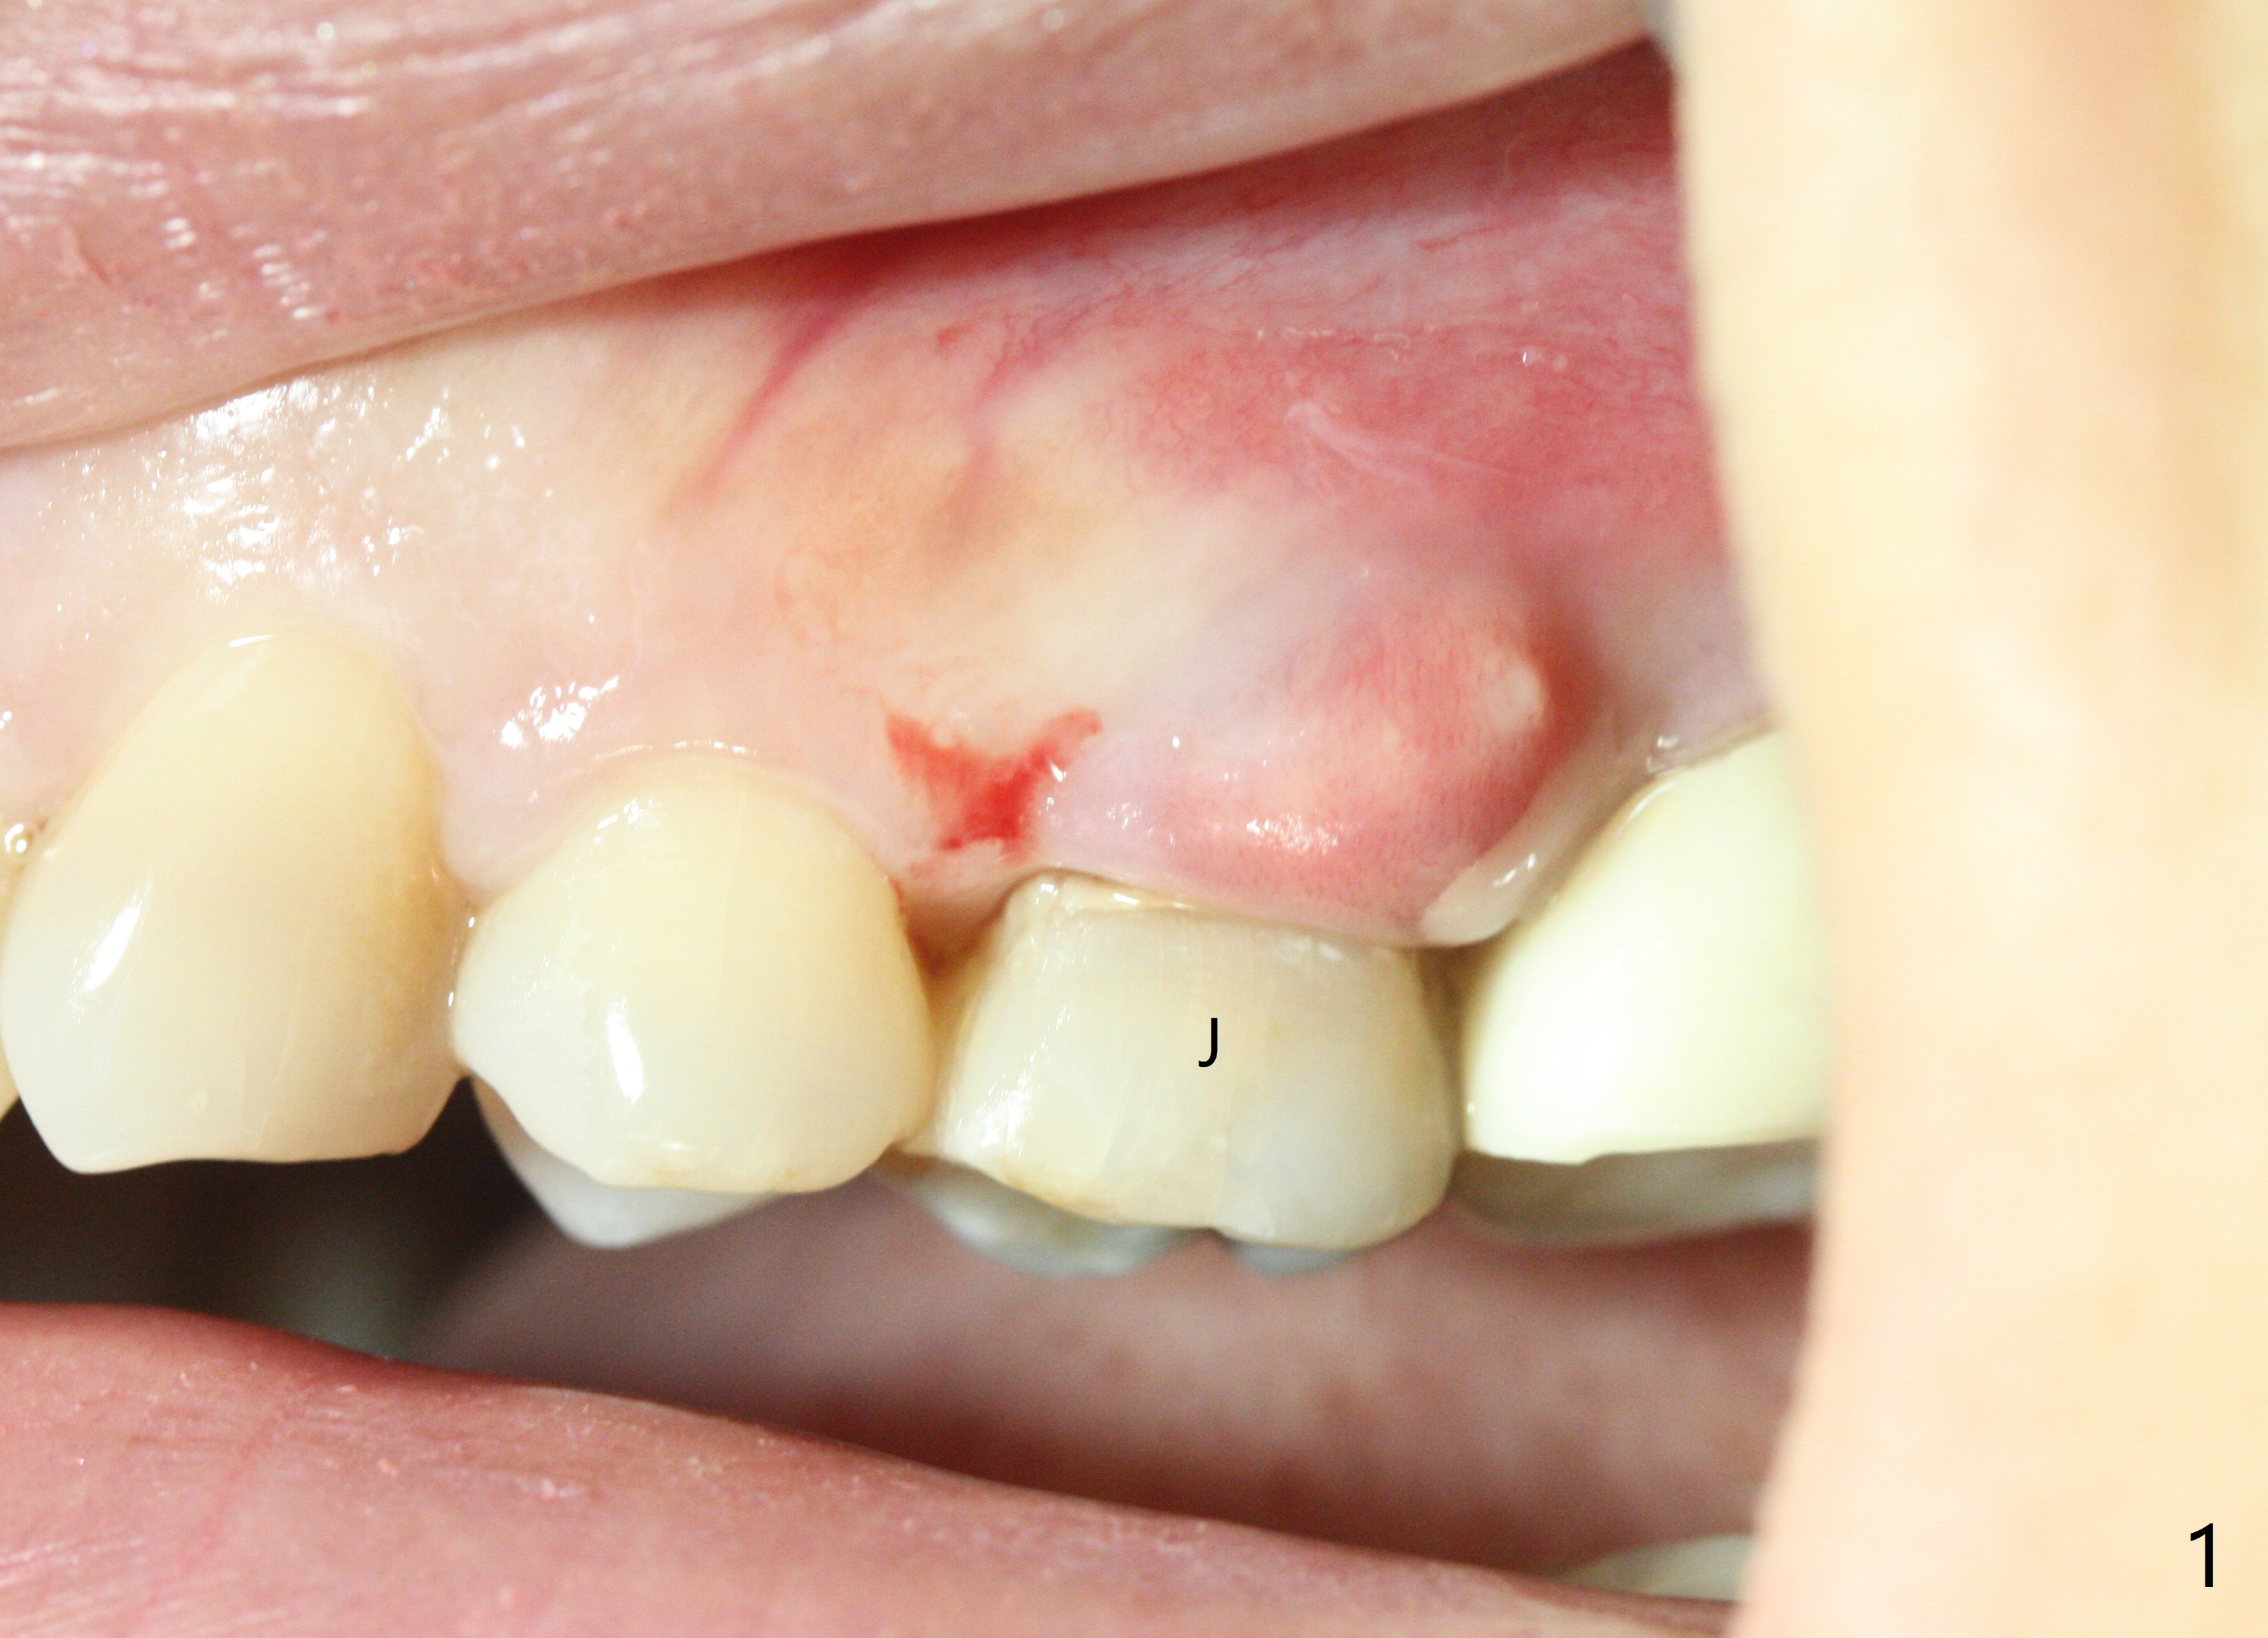

A 42-year-old woman requests extraction of the upper left 2nd primary molar with abscess (Fig.1,3,4). To avoid implants (for #30 as well in Fig.2) and improves cosmetics (anterior crowding), she chooses orthodontics with extraction of 2 more teeth in the other 2 quadrants. It seems necessary to have socket preservation so that the neighboring teeth have the bone to move to (Fig.5 without buccal plate collapse). In fact the coronal half of the buccal plate is resorbed. The bone regeneration is also important in case she changes her mind and ends up needing an implant. Return to Trajectory Xin Wei, DDS, PhD, MS 1st edition 05/17/2019, last revision 05/19/2019